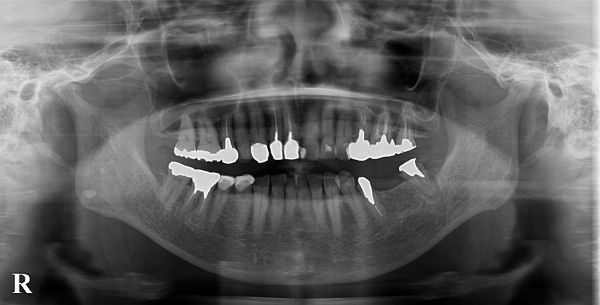

また、こちらが初診時のレントゲン写真になります。

左下5番目の歯も同様で、大きな金属の土台を外して虫歯を取ると、ほとんど歯茎の外側には健康な歯が残らない状態となります。また、レントゲン写真を見ると、とても太い金属の土台が入っているため、残っている歯がとても薄くなってしまっており、ブリッジで大きな力をかけた際に歯根破折(歯の根のヒビ)が起こる可能性が非常に高いことが予想されます。

また、下顎のインプラント治療を行う際は、下顎管という感覚神経(下歯槽神経)が入った管に注意をしなければなりませんが、今回は神経との距離も十分にあり、極めて安全にインプラント治療が行えるケースでありました。今回は、予算の都合上、2本のインプラントで2本の歯を作ることとしました。